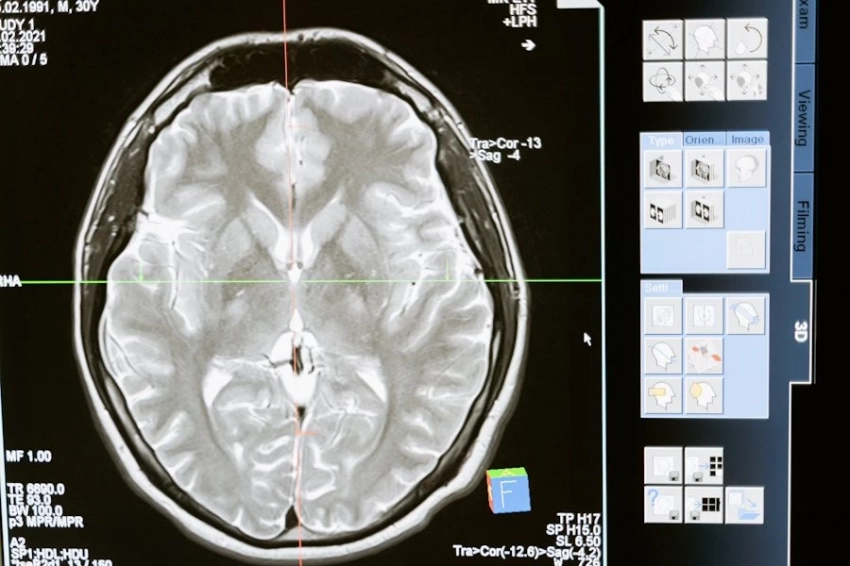

14 способов защитить мозг от деменции: результаты нового исследования

В августе 2024 года в журнале The Lancet были представлены результаты исследования, в рамках которого определены 14 факторов, снижающих вероятность развития деменции. Как отмечает издание Prevention, даже небольшие изменения в повседневной жизни могут существенно повлиять на здоровье мозга.